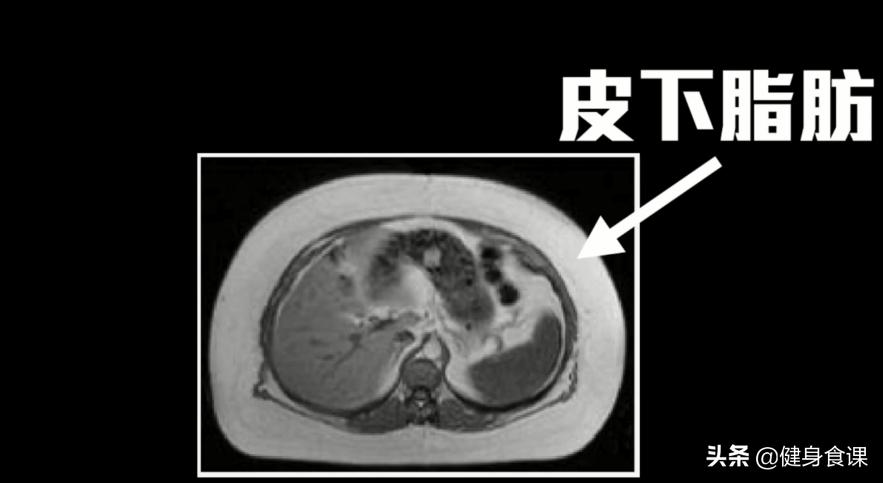

腹部的核磁共振也可以看出来:皮下脂肪从人本厚厚一圈变成比较薄一些手术本身非常的成功。

其实腹部脂肪也分为两种,一种的是手一捏就会捏起来的皮下脂肪,另一种则是附着在我们肠道、内脏周围的内脏脂肪。医学研究发现,内脏周围堆积的脂肪,肝脏里面的脂肪还有肌肉里面堆积的脂肪对于健康特别有害!

抽脂手术所能移除的呢,都是皮下脂肪,而内脏脂肪的一点都不会变少。也难怪,就算这些人抽了十公斤的脂肪,他们的健康,一点也没有改善。